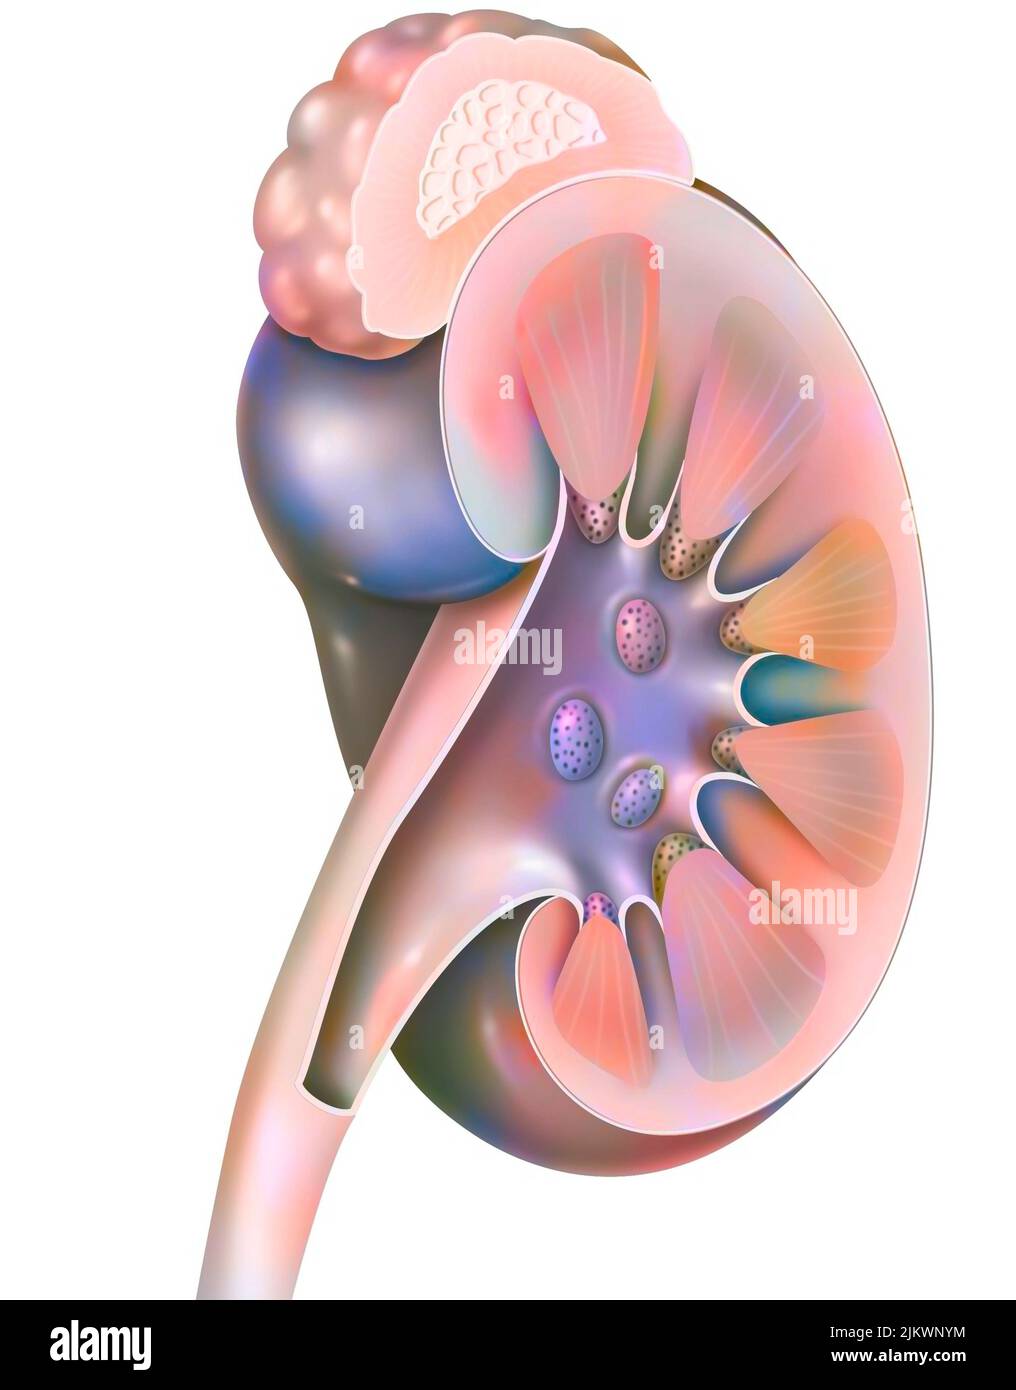

RM2WWBCW9–Reins en vue antérieure avec uretères surrénaliennes et artères et veines rénales. Le rein gauche est placé plus haut que le rein droit.